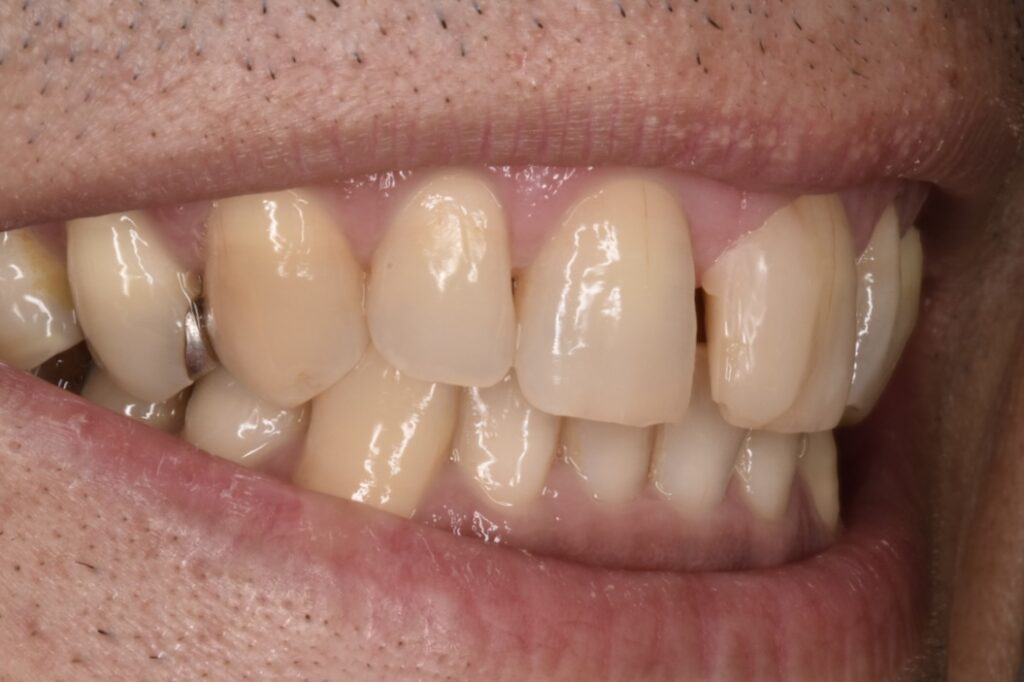

50代男性です。当院にご相談してくださる前に他院で前歯2本のダイレクトボンディング?を受けられたそうです。前歯2本の隙間は確かに白いレジンで埋められていましたが、本当に盛って作っただけのもので、違和感がかなり強かったそうです。

施術前

当院でタイレクトボンディング2歯のやりかえをご希望されて、2本でご契約してくださいました。他院のレジンは前日に取れたそうです。